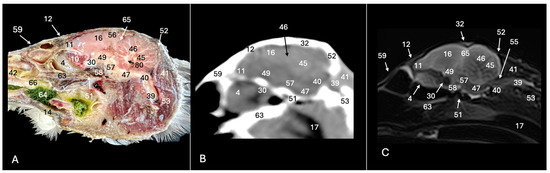

3. Result

3.1. Anatomical Sections

3.2. Computed Tomography (CT)

3.3. Magnetic Resonance Imaging (MRI)